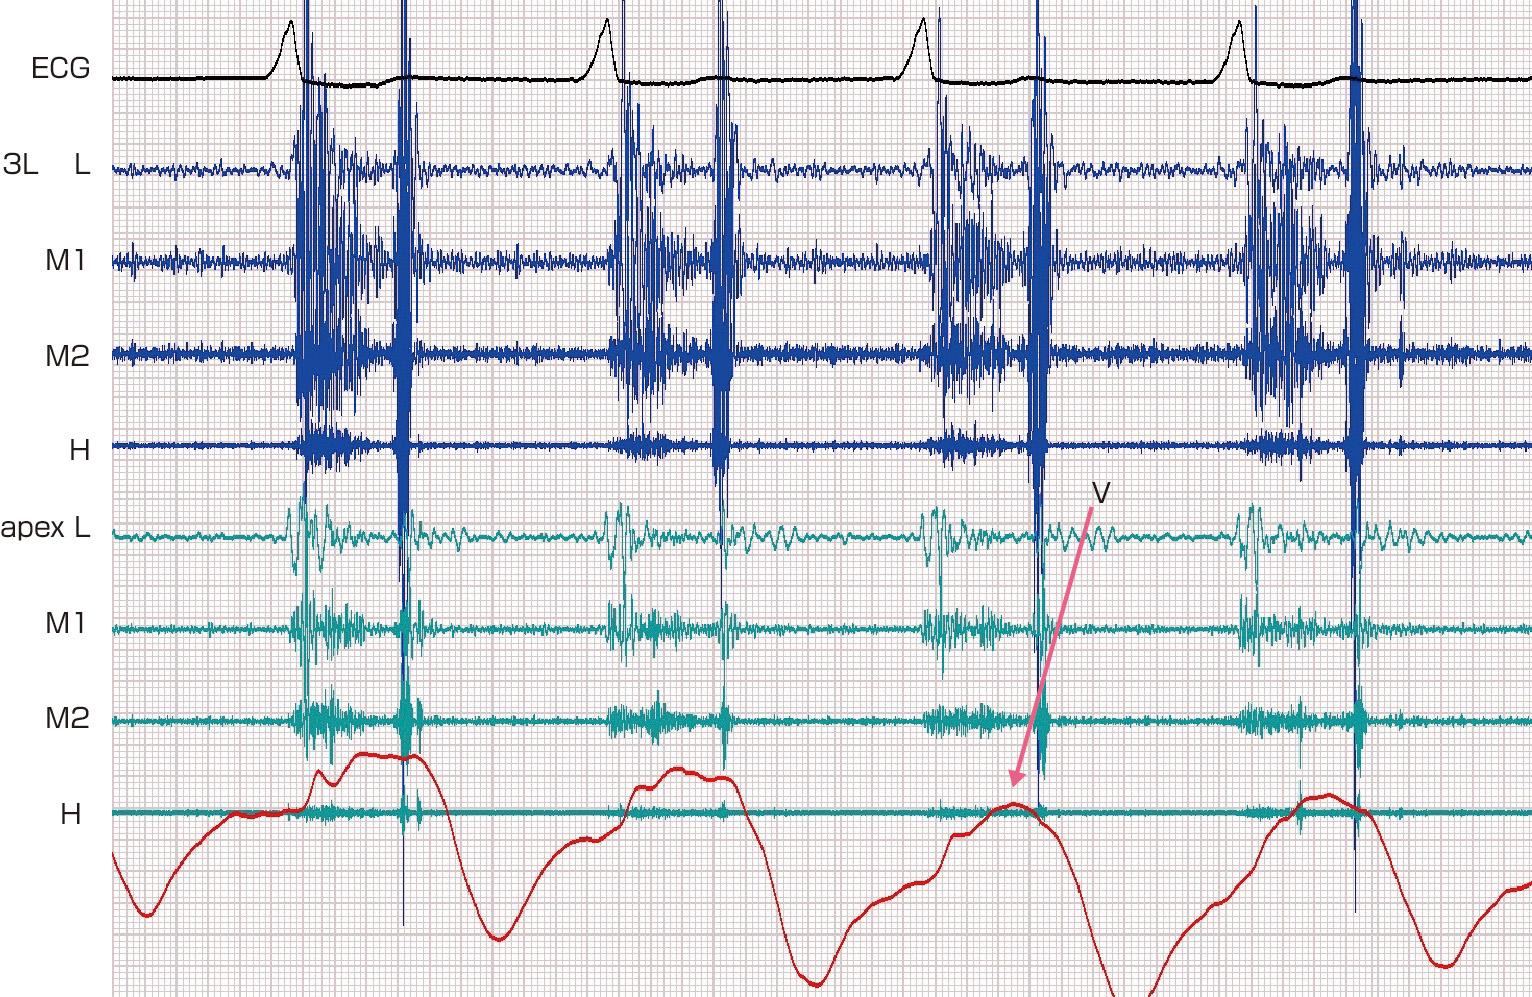

2ページ目) 「命をつなぐ行為」 “透析大国”日本、一方で進まない患者への理解 「“輸血に使われたくないから献血しない”という誤った知識も…」 | 国内 | ABEMA TIMES | アベマタイムズ, 朝倉書店『内科学』(第12版)デジタル付録,

朝倉書店『内科学』(第12版)デジタル付録, 楽天ブックス: いちからわかる!新NISA&iDeCo 2025年最新版 - 山中伸枝 - 9784295020677 : 本,

![[A12144612]カテーテルアブレーションのためのチャートで学ぶトラブルシューティング! [単行本] 山根 禎一](https://auctions.c.yimg.jp/images.auctions.yahoo.co.jp/image/dr000/auc0505/users/d4fab30473777a8019148ae00533fa27693af6d4/i-img350x500-1716469936foeqp3222191.jpg)